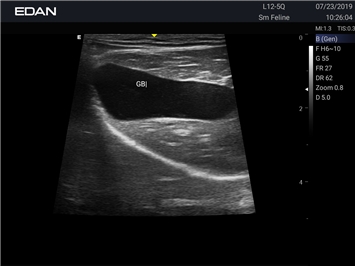

Новая эра УЗИ в ветеринарии. Диагностическая ультразвуковая система для ветеринарии, AX8 — это многофункциональная диагностическая ультразвуковая платформа с расширенными режимами визуализации, двумя сенсорными экранами с жестовым управлением и полным набором датчиков, которые соответствуют конкретным потребностям ветеринаров.

Профессиональный ветеринарный УЗИ аппарат EDAN Acclarix AX8 VET сочетает инновационные технологии визуализации с надежной конструкцией, специально разработанной для ветеринарной практики.

B-режим, Двухмерное сканирование:

Да

Общая визуализация:

Ветеринария: